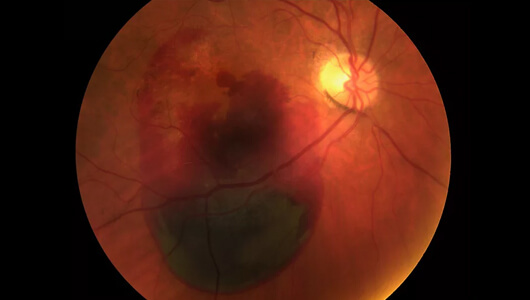

Ovo je prikaz mrežnjače drugog pacijenta - 27-godišnjeg programera koji je došao izliječiti astigmatizam laserskom operacijom.

Pomogla je neko vrijeme. Pacijent je mogao živjeti bez naočala.

Ali nakon godinu dana je morao proći još jednu operaciju. Vid mu se pogoršao jer je mnogo vremena provodio radeći ispred računala.